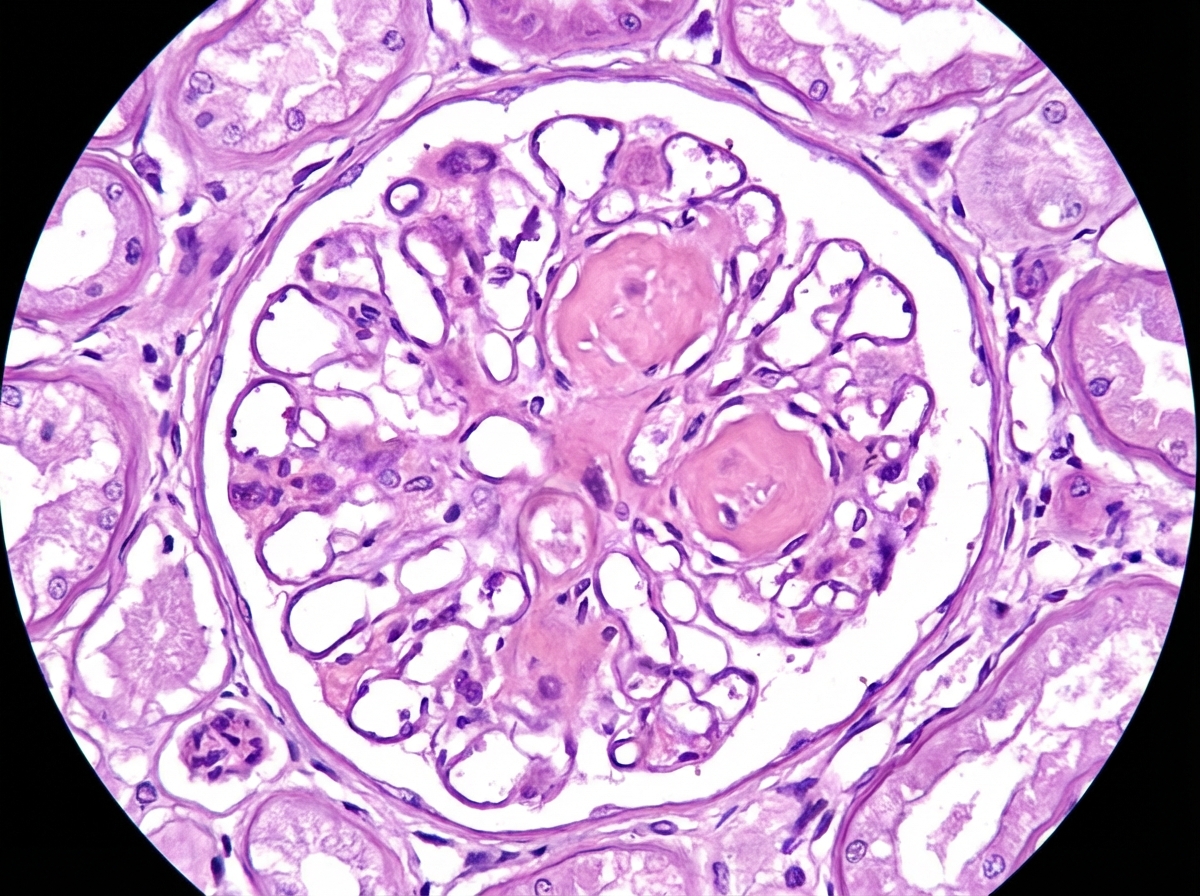

A 62-year-old man comes to the physician because of fatigue and decreased urine output for 2 weeks. He has not been to the physician for many years and takes no medications. Serum studies show a urea nitrogen concentration of 42 mg/dL and a creatinine concentration of 2.3 mg/dL. Urinalysis shows heavy proteinuria. A photomicrograph of a section of a kidney biopsy specimen is shown. Which of the following is the most likely underlying cause of this patient's symptoms?

A 49-year-old female with a long history of poorly controlled diabetes mellitus visits her primary care physician with 2+ non-pitting edema in her legs. The patient has a serum creatinine of 2.9 mg/dL and a blood urea nitrogen of 61 mg/dL. A 24-hour urine collection reveals 8.5 grams of protein. A renal biopsy is obtained. Which of the following histologic findings is most likely to be seen upon tissue analysis: